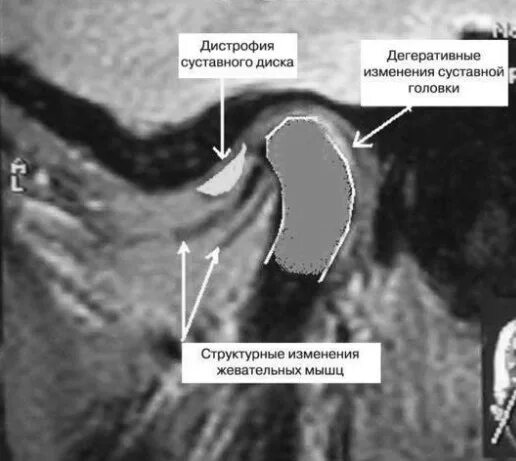

Дислокации дисков